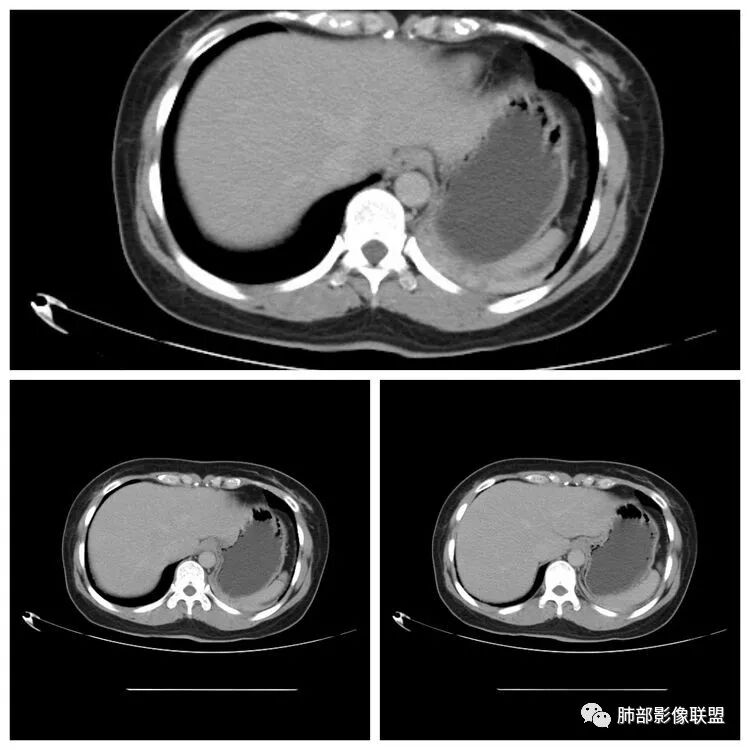

下面看第三部分了,3月20日补增强扫描:

M-Imaging :错了,这么大,膈肌后方南边:定位?定性?Shelia:肺外。感觉病灶是个扁平状,虽然没有蛇纹血管征,但是延迟强化,怀疑纤维来源,考虑sft

M-Imaging :肿块与胸膜夹角是锐角,有分叶,觉得肺内Lotus:mpr重建再看一下南边:与支气管有关系吗Shelia:没有关系。与胸膜分不清

Coke with ice:与肺韧带有关系。与肺韧带的夹角呈钝角,感觉有胸膜尾

宇宙星空:糊墙关系:

南边:边缘这么光滑,无分叶,与胸膜关系密切

宇宙星空:延迟明显强化,其内可见条索状低密度,支持SFT

一米阳光:与膈胸膜关系密切,肺受压。考虑SFT

CT表现:1.多为来自胸膜单发肿块,轮廓较光滑,一般无分叶,可有包膜,可以有胸膜尾征。少数胸膜SFT可表现为带蒂肿块,为本病较为特征性表现。2.当肿瘤较小(小于5cm)时,平扫密度较均匀,为软组织密度,增强扫描呈轻中度均匀强化,少数肿瘤强化较明显。3.随着肿瘤的增大,发生粘液变性、囊变坏死概率增加,多表现为密度不均匀,并可有钙化,增强为轻中度不均匀强化,常表现为“地图样”。

潘军平老师关于定位点评——我们判断肺内肺外的依据:1、与胸膜的关系。主体在外面,宽基底与胸膜连接,胸膜掀起一般是肺外的依据。2.、与肺内结构的关系:附近血管、支气管被推移,未进入病灶(无血供的良性病变有时候要警惕除外),提示肺外。3、血供,肺部来源的一般肺部血供(隔离症除外,恶性肿瘤有时候会有差异,孤立性纤维瘤血供可以肺内来源)。